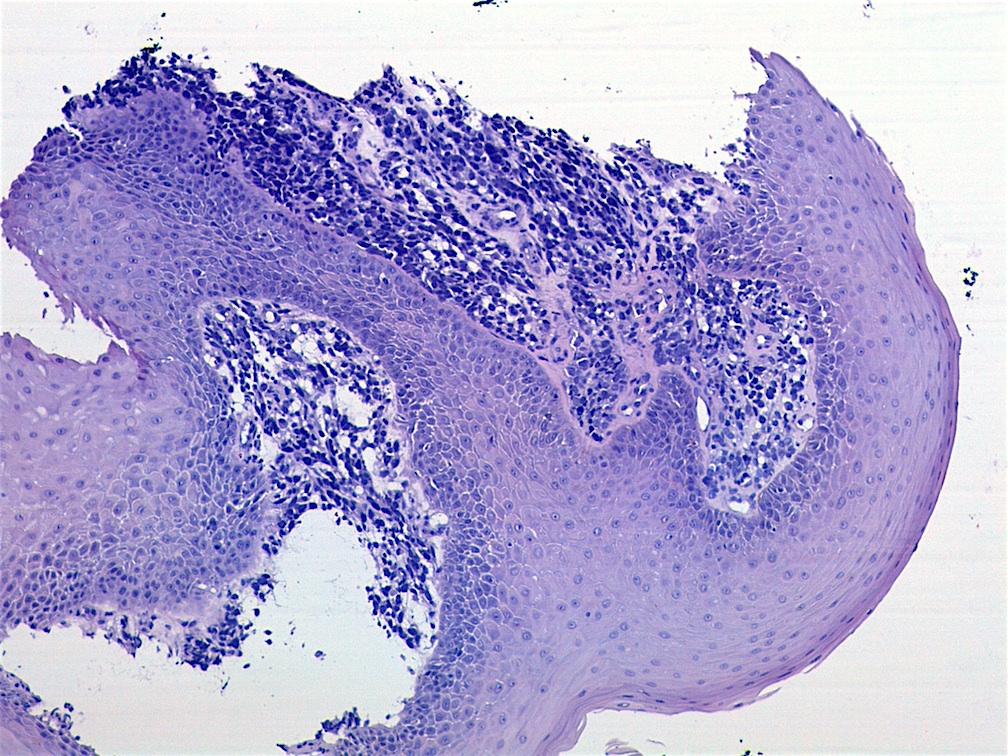

- Botryoid variant frequently shows a cambium layer: a hypercellular zone immediately beneath the epithelial surface

- Cells are undifferentiated, round or spindled with minimal cytoplasm, frequent mitotic figures

- Deeper layers of the tumor are typically less cellular but overall conform to the histology of embryonal rhabdomyosarcoma (ERMS) with variation by region

Microscopic (histologic) images

Contributed by Carolina Martinez Ciarpaglini, M.D., Ph.D. (Case #276) - tonsillar mass

AFIP images - botryoid variant